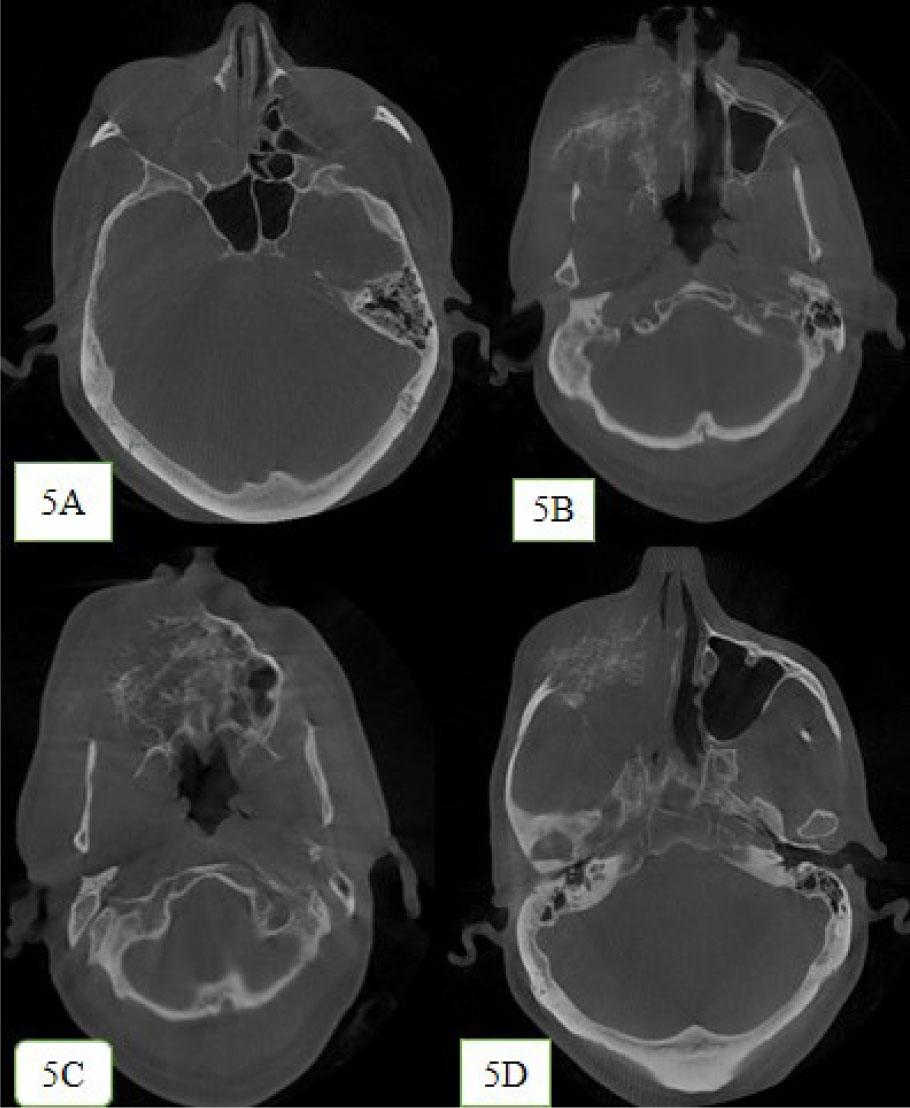

The lesion was seen crossing the midline in the posterior region with complete destruction of floor of orbit and cortical bone on the right side (Figure 5A–5D). Haziness was seen within the substance of sphenoidal sinus, right maxillary, ethmoidal, and frontal sinuses, indicating the involvement of paranasal sinuses.

Destruction pattern of the lesion in axial view. 5A: Destruction of the right lateral wall of nasal cavity and inferior turbinates. 5B: Mixed radiolucent radiopaque lesion caused destruction of anterolateral and posterolateral wall and floor of right maxillary sinus and nasal cavity. 5C: The mixed radiolucent radiopaque lesion seen crossing the midline of the palate at the posterior region. 5D: Mixed radiolucent radiopaque lesion produces sunburst appearance at the right zygoma region